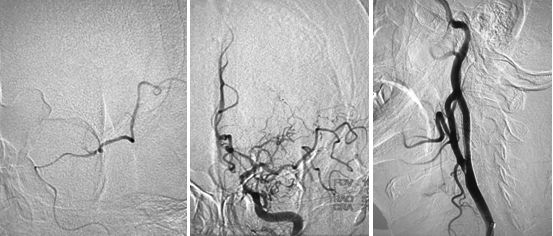

DSA结果提示:左侧颈内动脉次全闭塞,远端未见显影,左侧大脑中动脉闭塞,前交通动脉开放,左侧椎动脉起始部重度狭窄(图3-5)。

图3

图4

图5